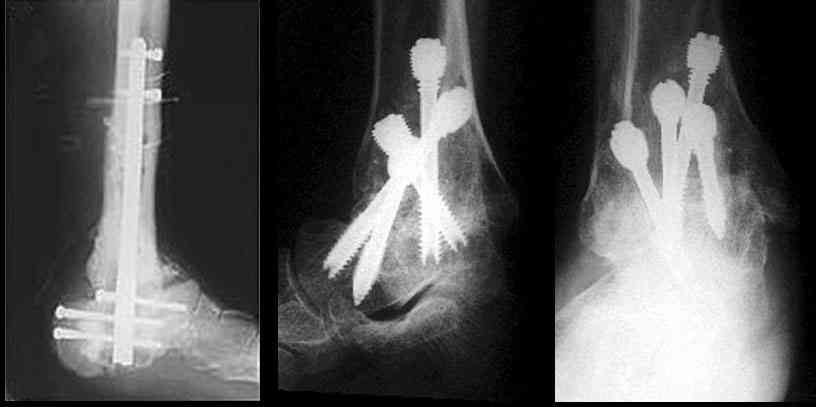

Можно: 65-летняя пациентка, оперирована по поводу несросшегося в гипсе перелома лодыжек с патологической вальгусной установкой стопы и выраженным нарушением опрной функции. Оперирована через 6 месяцев после травмы. Рентгенограммы через 4 месяца после операции.

Существуют специальные системы для артродеза голеностопного сустава. См. приложение

Уважаемый А.Семенистый. Складывается впечатление, что вы выполнили трехсуставный артродез, уж больно длинные блокирующие винты. Не мешают ли они пациентке при ходьбе?